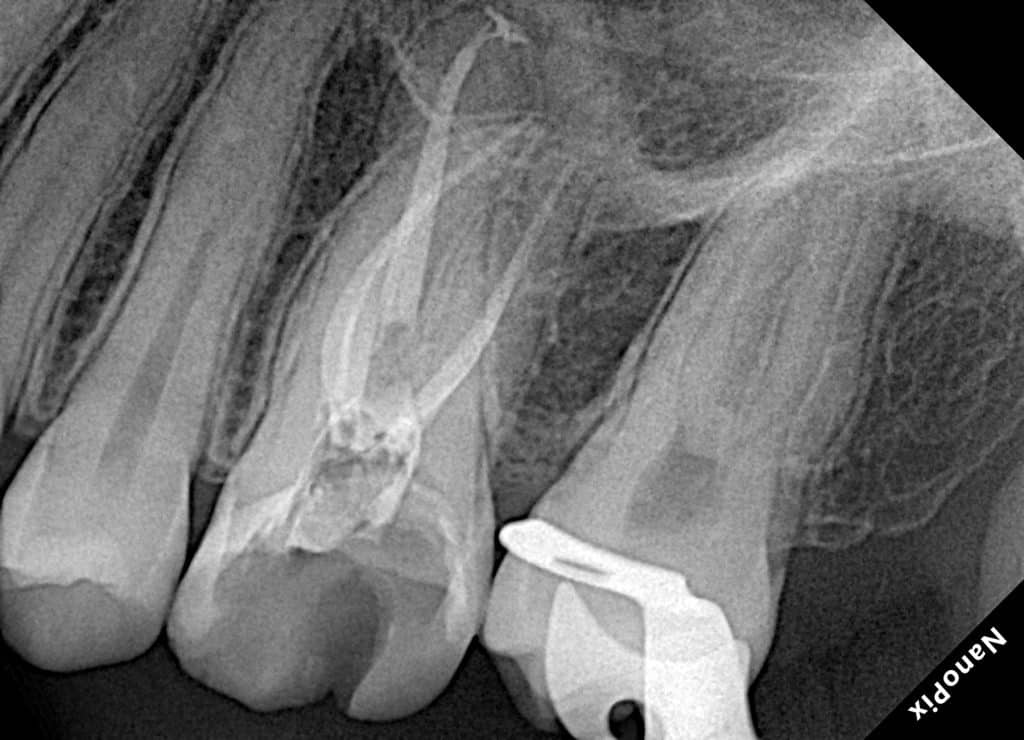

UL6 with SAP and deep palatal caries.

Caries removal and cleaning to determine the margin height then margin elevation as a pre endo build up under rubber dam isolation, endodontic treatment in the same visit to minimize flar up and direct restoration was done in the second visit.